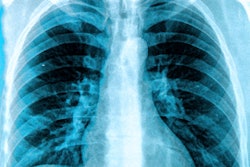

The company has secured a supply contract with TeleDiag in France and the Portuguese League Against Cancer, it said. TeleDiag is France's largest teleradiology group; it will use Lunit's Insight CXR, Lunit said. The Portuguese League Against Cancer will use Lunit's Insight MMG to analyze 100,000 mammograms each year over the next three, according to the firm.